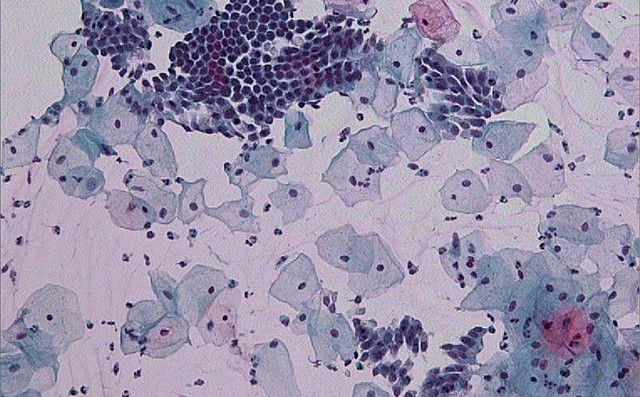

Kitajska raziskovalna skupina je z analizo DNK brisov materničnega vratu določila vrstno sestavo bakterij, ki so bile del vaginalne mikrobiote pri 45 neokuženih in 90 ženskah, okuženih s HPV. Izkazalo se je, da več ni vedno bolje. Kitajske znanstvenice in znanstveniki so najmanjšo vrstno pestrost določili v mikrobioti neokuženih žensk. Vrstna pestrost je bila višja pri posameznicah s trajno okužbo v primerjavi s posameznicami s prehodno okužbo.

Pri neokuženih v mikrobioti dominira ena bakterija iz rodu Lactobacillus. Znano je, da laktobacíli vzdržujejo nizek pH v nožnici, kar otežuje naselitev drugih bakterij, pa tudi okužbo celic povrhnjice materničnega vratu z virusom HPV. Pri dobri polovici okuženih posameznic je kitajska raziskovalna skupina odkrila, da je dominantna vrsta bakterije prav tako iz rodu Lactobacillus. Pri ostalih okuženih pa je bila dominantna bakterijska vrsta iz drugega rodu, predvsem Sneathia in Prevotella

Vir slike: https://upload.wikimedia.org/wikipedia/commons/thumb/d/d6/Pap_test_wnl…